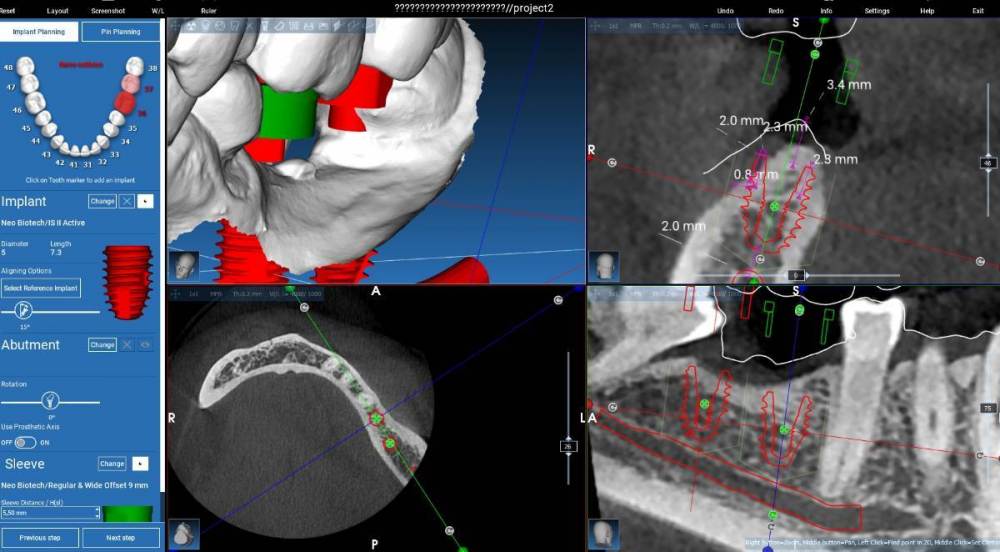

Fin Опубликовано 21 августа, 2023 Поделиться Опубликовано 21 августа, 2023 Здравствуйте коллеги. Появился такой клинический случай. Как вы считаете поможет ли установка 2 импл. штрауман 4.1 на 6 с полированной шейкой 1.8 в данной ситуации? На скриншотах представлен необиотек это как второй вариант 4.6 -4х 7.3 с полировкой 0,5 и 4.7- 5х7.3 с полировкой 1.3 . Штрауман будет на 0,5 мм выше коронально. Спасибо Ссылка на комментарий

Fin Опубликовано 21 августа, 2023 Автор Поделиться Опубликовано 21 августа, 2023 (изменено) 1 час назад, koreandr сказал: В дистальный вроде как WN 6 мм войдет. Спасибо.Вы имеете ввиду диаметр 4.8? Я в Штрауманах плоховато разбираюсь, но для таких клин случаев нужно. 1 час назад, stommm сказал: Как вариант оба 5х7.3. У 46 шейку повыше. И 47 лучше вестибулярнее. Дефицит десны язычно потом намного сложнее решить будет. Благодарю. Оба Необиотека 5x7.3 с полировкой 1.3? Изменено 21 августа, 2023 пользователем Fin Ссылка на комментарий

stommm Опубликовано 21 августа, 2023 Поделиться Опубликовано 21 августа, 2023 15 минут назад, TIGER сказал: Для нео 7.3 кости надо 10 мм для заглуба Зачем если шейка 2.3? Ну и судя по скринам влезает по высоте точно. Но тут коронок не видно. Выглядит будто 47 в перекрес выйдёт. Штрауманн тоже можно. Дистально 6 мм. Медиально 6 или 8 (рисовать с учётом коронки и выбирать) Ссылка на комментарий

Fin Опубликовано 23 августа, 2023 Автор Поделиться Опубликовано 23 августа, 2023 21.08.2023 в 22:07, stommm сказал: Я нео не работал, но в каталоге видел с 5.0 с шекой 2.3. Попробуйте его нарисовать в планировщике и посмотрите как встанет 21.08.2023 в 21:06, TIGER сказал: @Fin регулярно ставлю 4 и 6 мм ,никаких проблем В моем случае поставили бы два 6мм штраумана? 21.08.2023 в 15:47, koreandr сказал: Так точно) Здравствуйте коллеги. Спасибо за ваши ответы. В планировщике, к сожалению нет импланта 5х7.3 с полировкой но по сути длина такая же. При планировании у пациентки получается перекрестный прикус- так и есть. Подгрузил прикус и немного поправил. Ссылка на комментарий